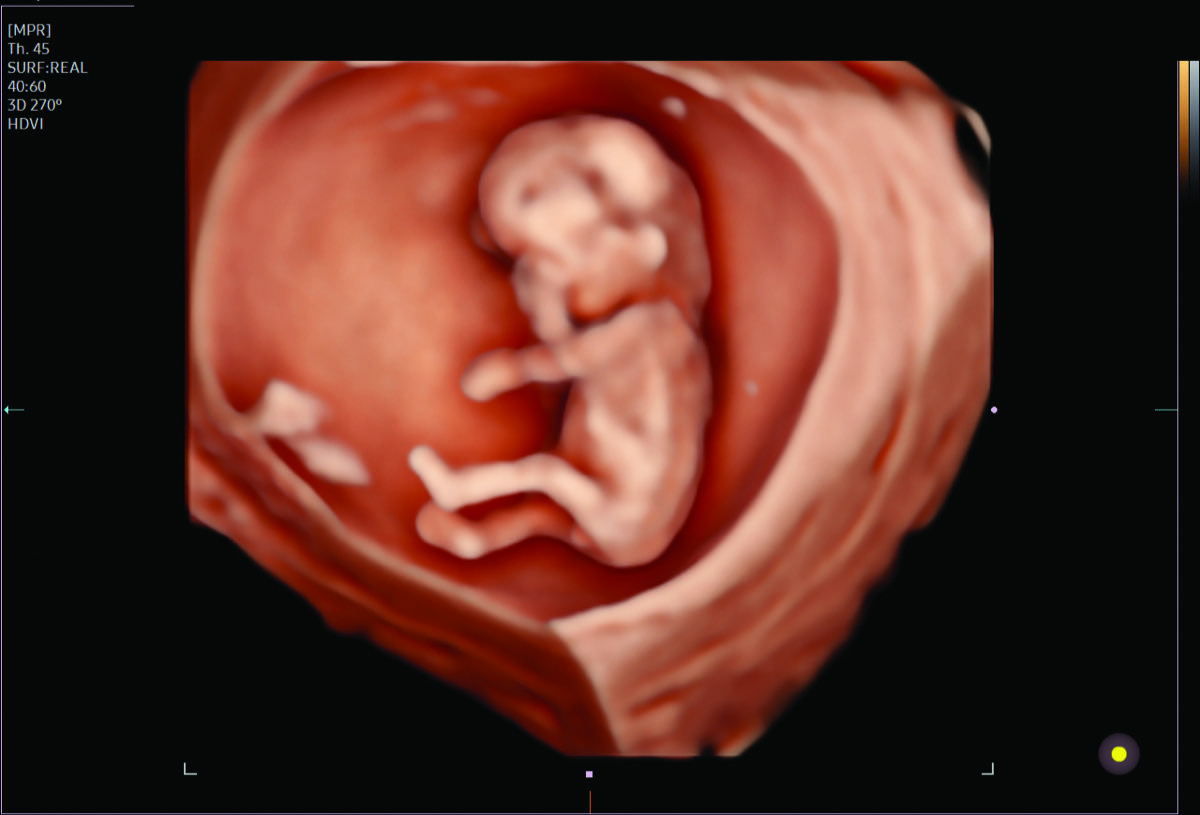

Comprehensive, advanced and expert MFM care for high-risk pregnancies

- Multiple births

- Fetal anomalies